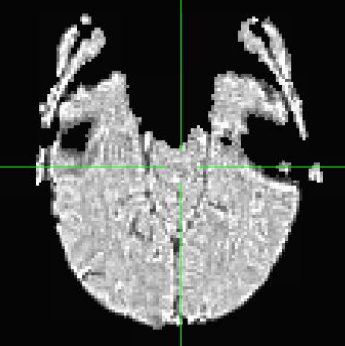

I am following up on the forum thread partial coverage alignment failure from January 2024 that seemed to stop because of technical issues. I am having a very similar issue since I am also trying to acquire a few BOLD fMRI slices including the hippocampus.I have only tried afni_proc so far, both on MNI (i.e. with tlrc option) and on subject space (ithout tlrc option). Unless you think it would be better to focus on MNI script, I will focus on T1w space since I am running only one participant to tune the parameters for now.

But when checking for EPI to Anat alignment, it looks like follows (almost like applying re-obliquing twice):